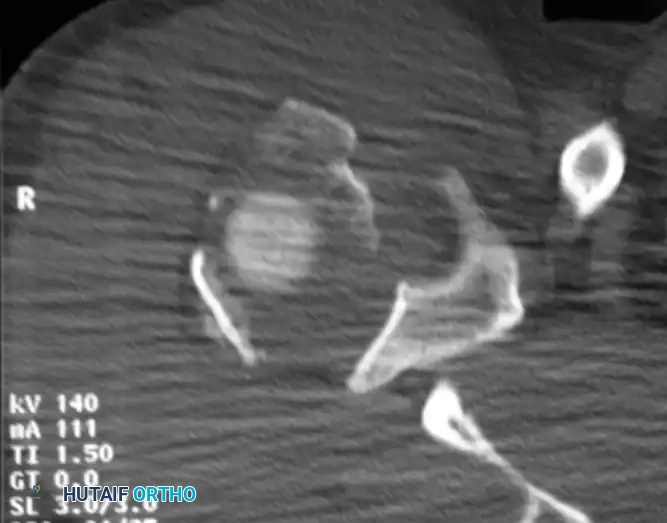

If the amount of displacement of the humeral head or tuberosity fragments remains unclear on plain radiographs, an axial CT scan with 2-mm sections and 3D reconstructions is strictly indicated. CT is invaluable for preoperative planning, particularly for assessing head-splitting fractures, tuberosity comminution, and glenoid rim involvement.

Fig. 54-12 CT scan of humeral head–splitting fracture.